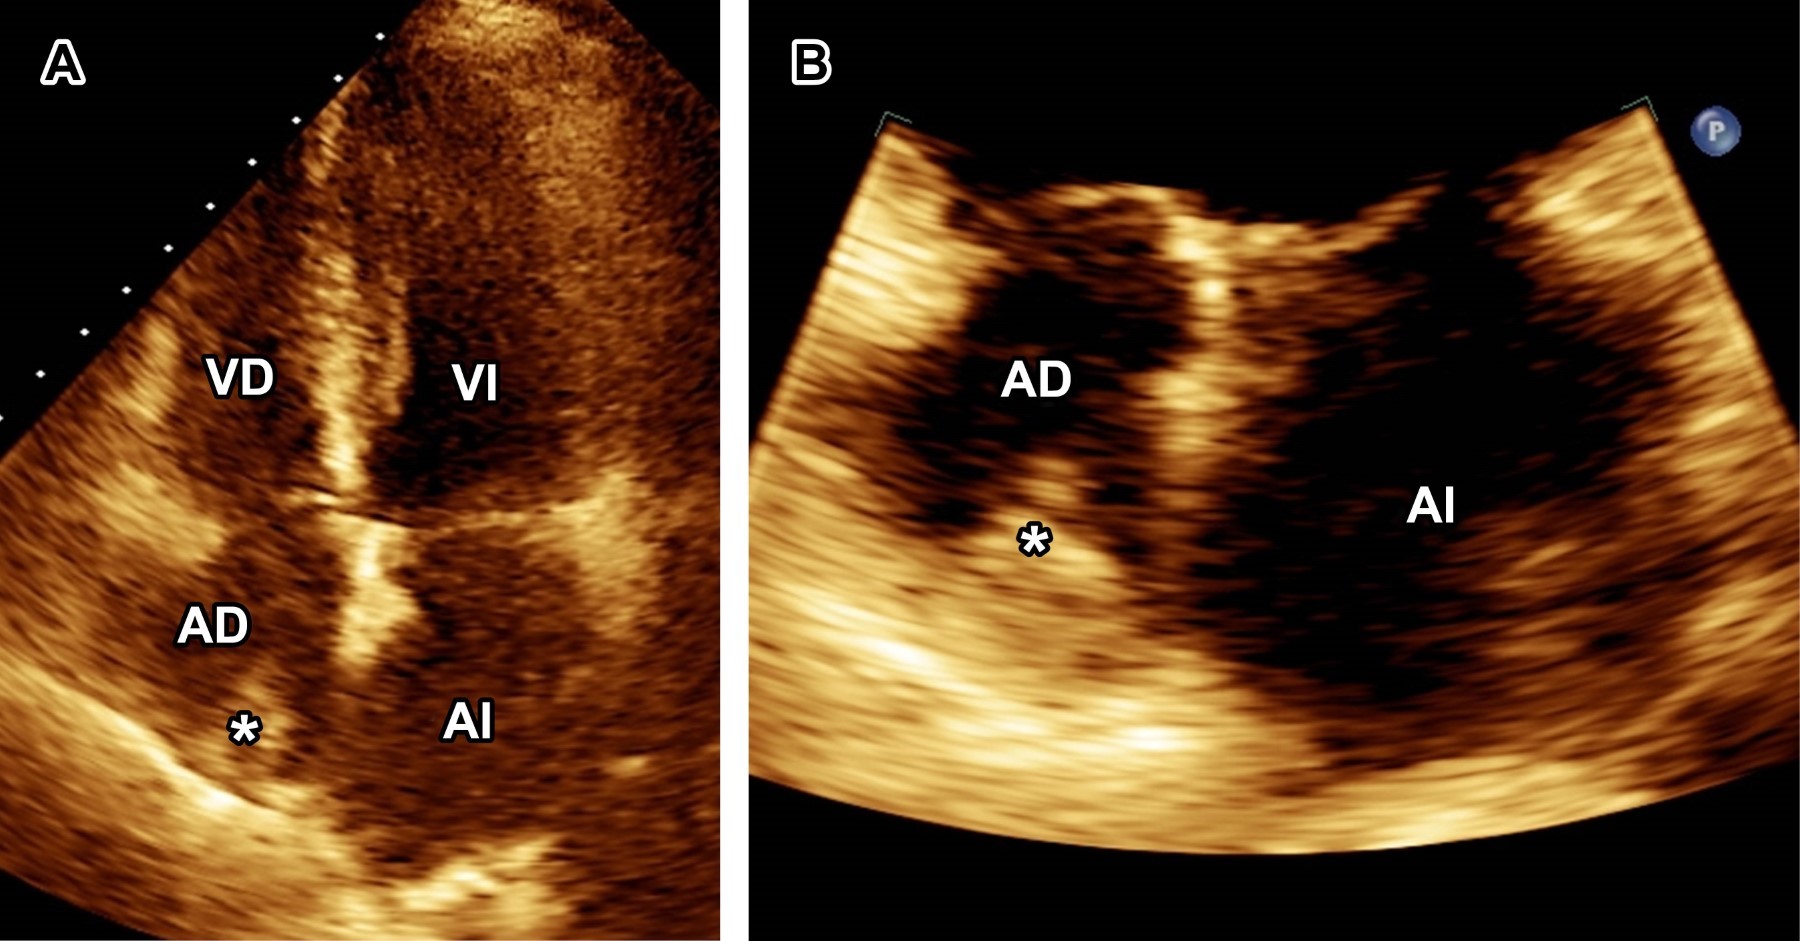

A la exploración física, ruidos cardiacos y respiratorios se auscultaron sin alteraciones. Laboratorios solo reportaron anemia (hemoglobina 8.7 g/dL). Ante sospecha de EI se tomaron hemocultivos y se inició tratamiento con vancomicina más ceftazidima. El ecocardiograma transtorácico (ECOTT) con mala ventana acústica mostró catéter de hemodiálisis engrosado con vegetación en la aurícula derecha (Figura 1), y se realizó ecocardiograma transesofágico (ECOTE), observándose vegetación en el catéter de hemodiálisis así como en aurícula derecha y sin compromiso valvular (Figura 2).

Figura 2